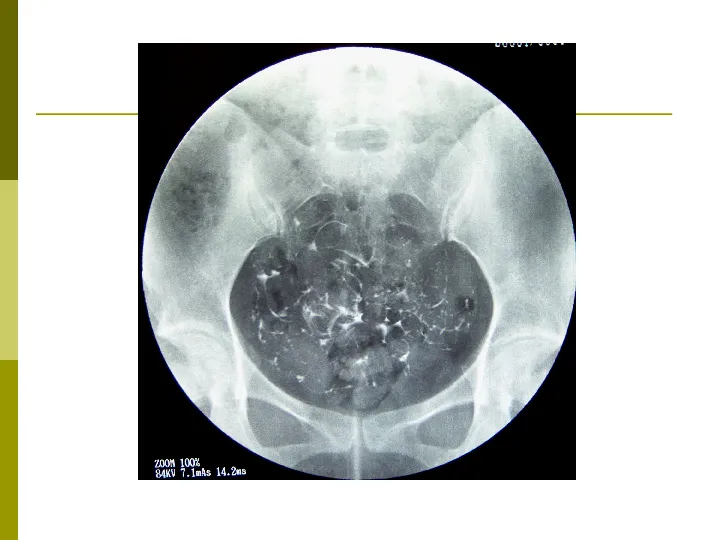

>【影像PPT】子宫输卵管造影术

【影像PPT】子宫输卵管造影术